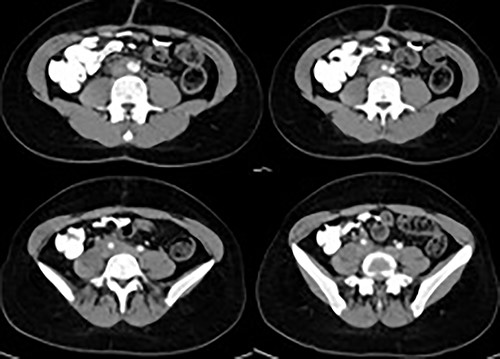

A 22-year-old with a history of polycystic ovaries and mesenteric resection, 6 months ago, was hospitalized for flatulence, indigestion, vomiting, anorexia and weight loss. He underwent computed tomography (CT) of the abdomen (Fig. 1), where a mass encloses the abdominal aorta and the arterial and venous axes as well as the right ureter. During the operation, a peritoneal tumor mass was found, which surrounds the lower part of the abdominal aorta and the pelvic vessels. A rapid biopsy was sent and the response to Castleman’s disease surprised the surgical team, who requested a vascular surgeon to be present. The mass was removed from the vessels, followed by appendicectomy and resection of the aortic lymph nodes (Fig. 2). The patient had a normal postoperative course and left the hospital on the fourth day after the operation.

CT of the abdomen revealed a mass encloses the abdominal aorta and the arterial and venous axes as well as the right ureter.